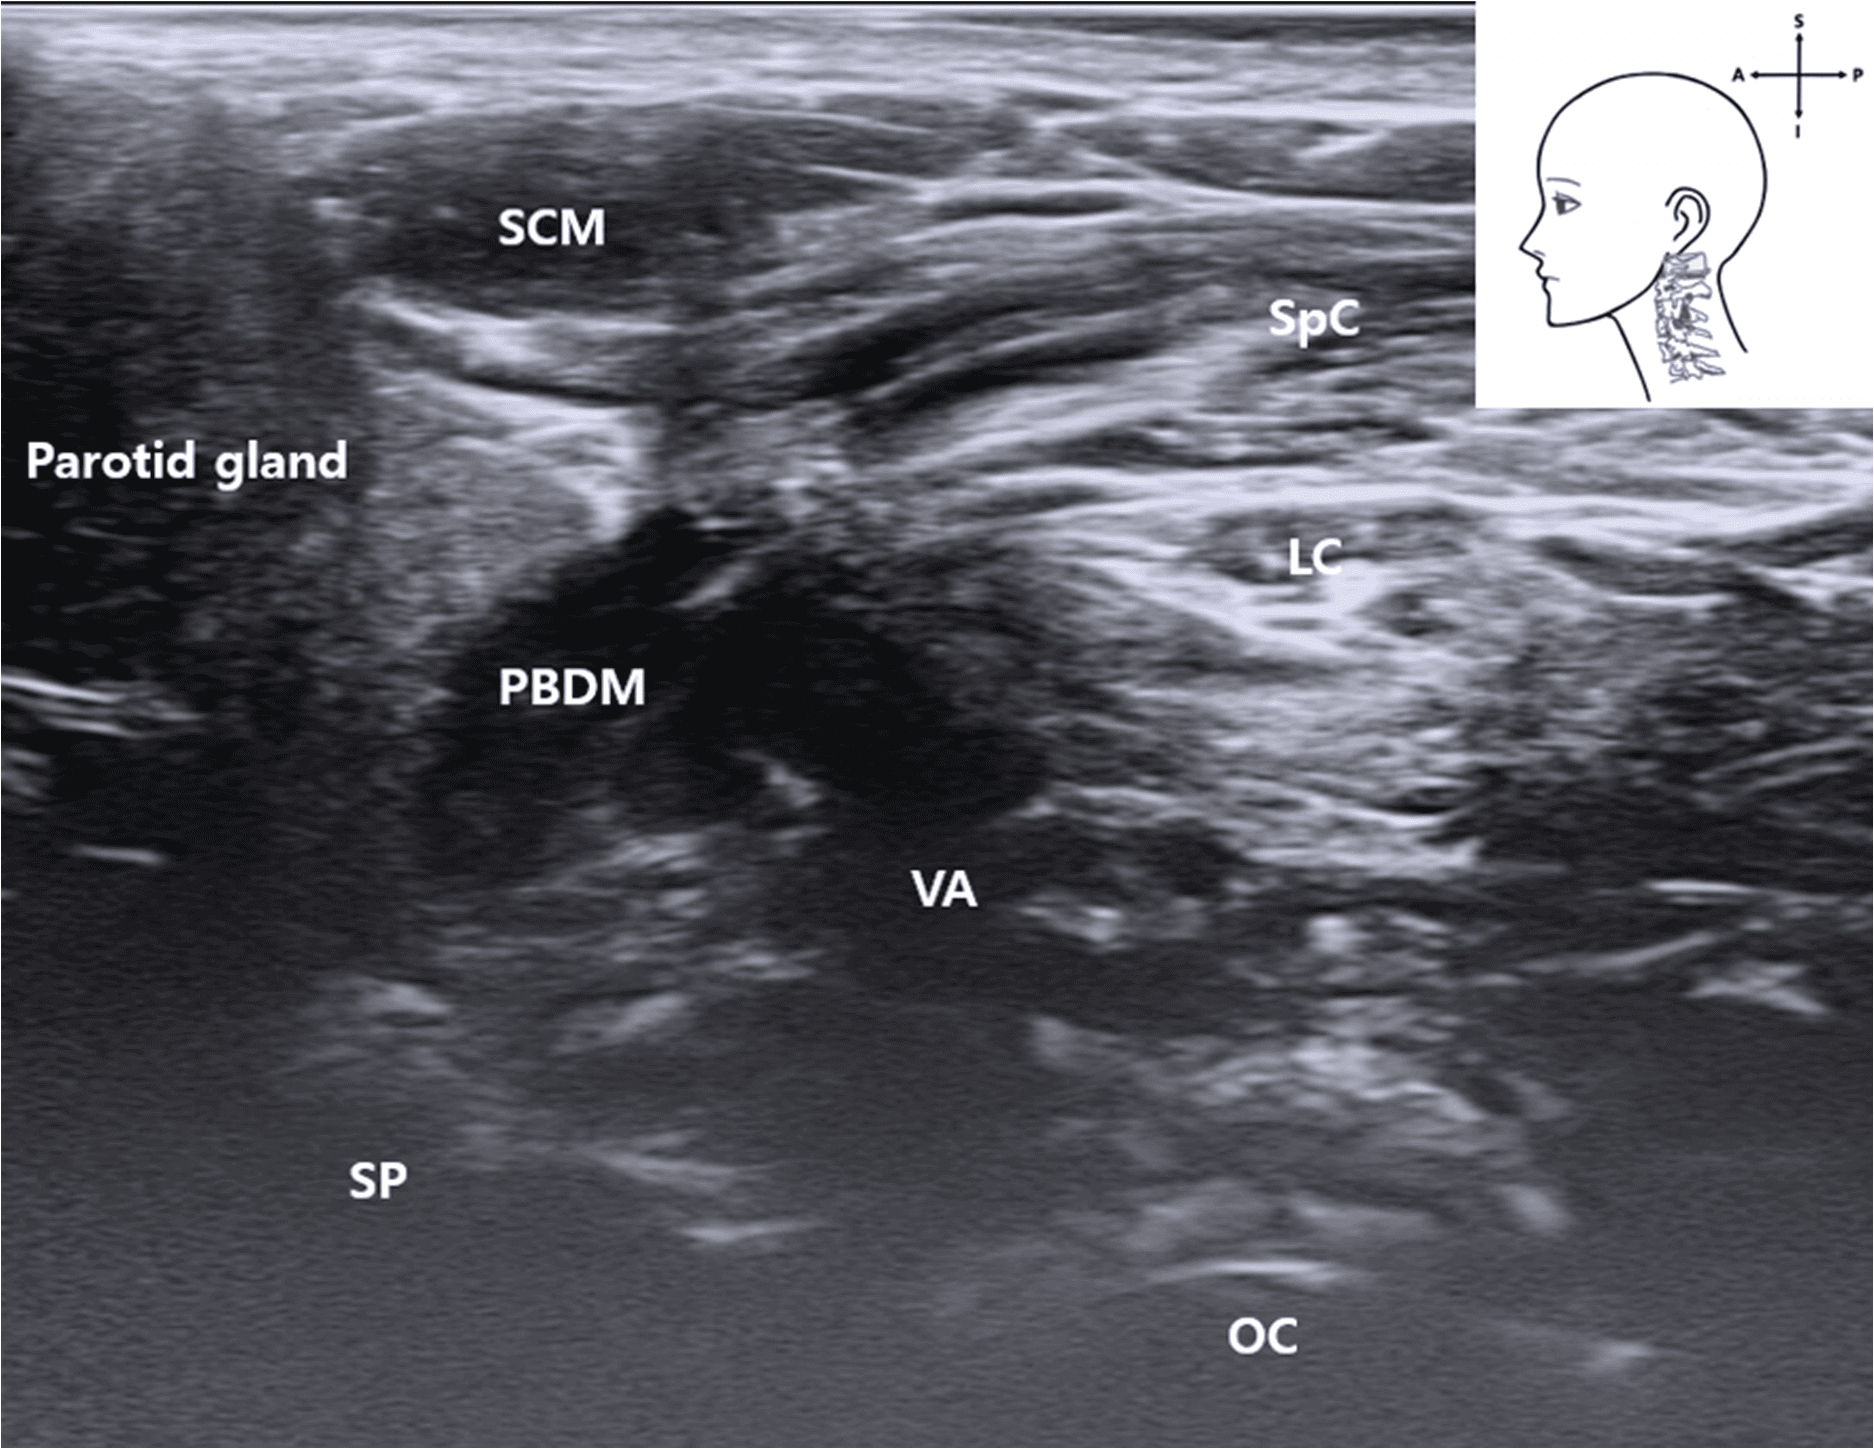

안면마비 - Ultrasound image showing the VA located deep between the posterior belly of the Figure 4. Ultrasound image showing the VA located deep between the posterior belly of the digastric muscle and occipital condyle. The SCM muscle lies superficially. This image was obtained with the probe tilted superiorly using a heel-toe maneuver to visualize the upper cervical region. SCM , sternocleidomastoid muscle; PBDM , posterior belly of digastric muscle; SpC , splenius capitis muscle; VA , vertebral artery; OC , occipital condyle; SP , styloid process; LC , Longissimus capitis muscle); blue rectangle, probe position.